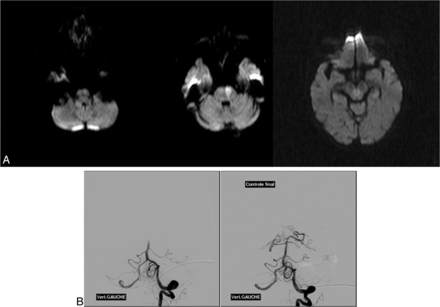

An 88-year-old woman who had right hemiparesis, vertigo, dysarthria, and vomiting. Pretreatment DWI (A) shows an extensive lesion in the left pons (brain stem score, 2) with a distal basilar clot on DSA (B) recanalized after IV thrombolysis and a thrombectomy (TICI 3). The time from symptom onset to recanalization was 336 minutes (4 hours 63 minutes). At day 180, the outcome was favorable (mRS 0).